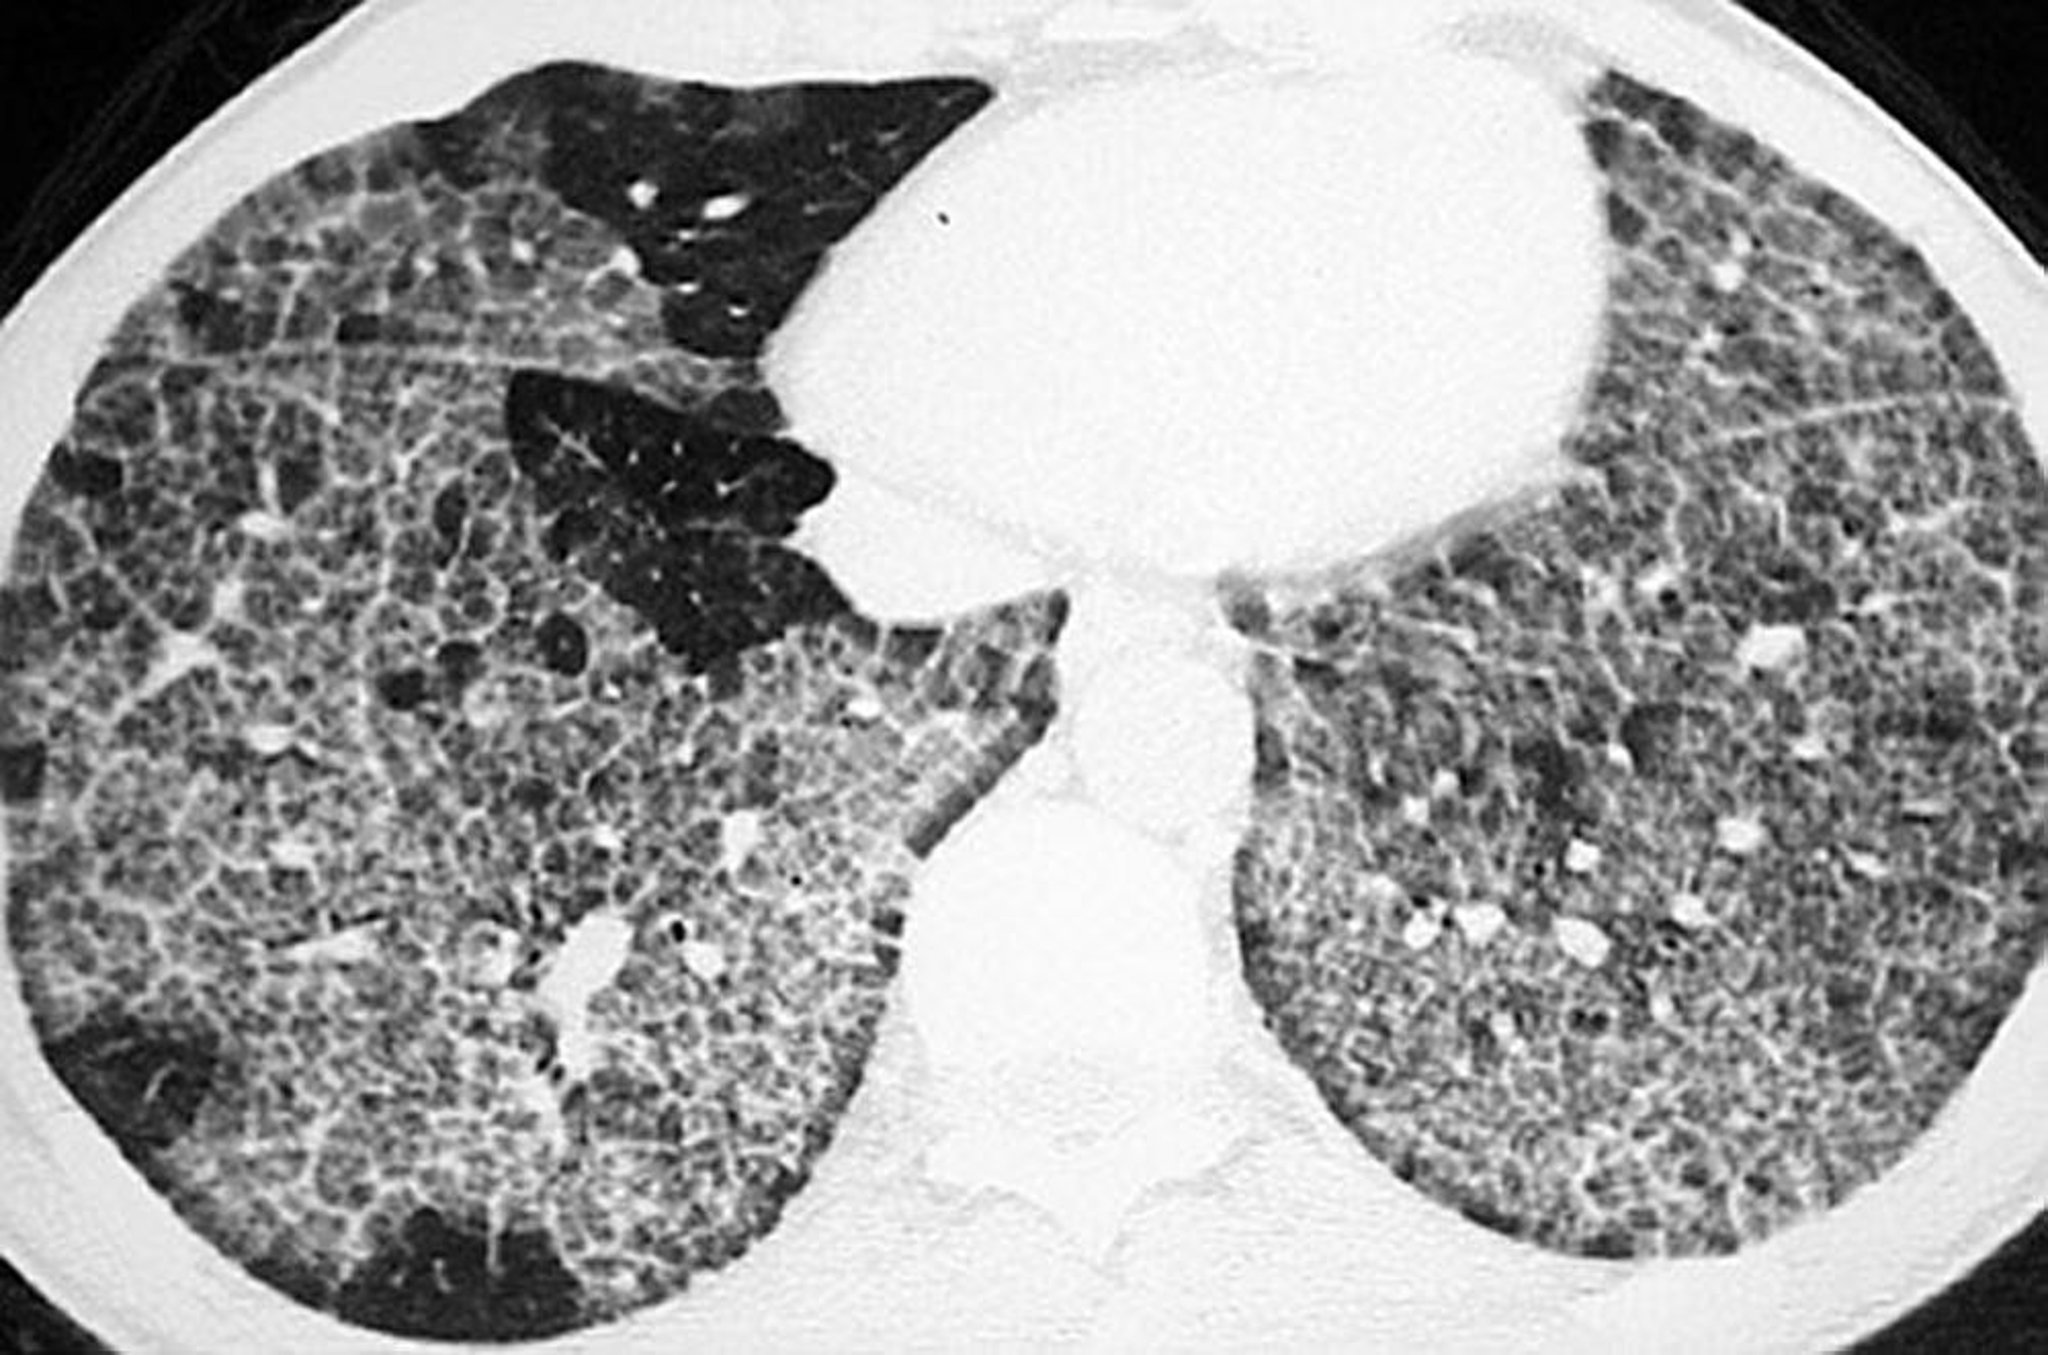

Pulmonary Alveolar Proteinosis (CT Scan)

High-resolution CT shows ground-glass opacification and thickened intralobular structures and septa in polygonal shapes ("crazy-paving").

Image courtesy of Talmadge E. King, MD.